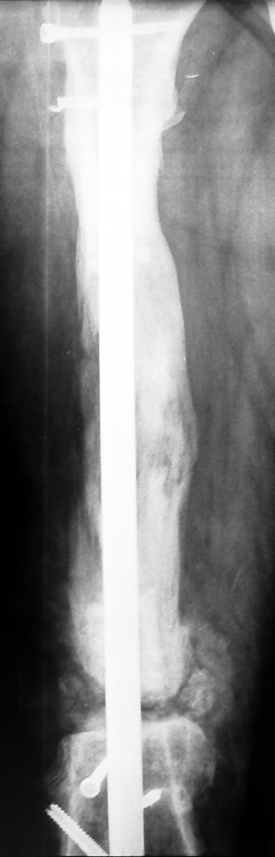

The duration of external fixation (external fixation index) depends on the amount of distraction required, and the extremity is prone to complications during this period. After the distraction phase is completed, the external fixator remains in place during the consolidation phase, which lasts twice as long as the distraction phase; but this period is hardly tolerated. If the external fixator is removed before sufficient consolidation is achieved, fractures, deformity and shortness will be the result. In our department, ‘lenghthening over nail’ method is used in order to decrease the external fixation index and increase patient comfort and activity level. In this method, the intramedullary nail is statically locked after the completion of the distraction phase, and external fixator is removed. The extremity is stabilized by the intramedullary nail during consolidation phase. In this way, complications due to long external fixation index or early removal of the external fixator are avoided.

Case 2